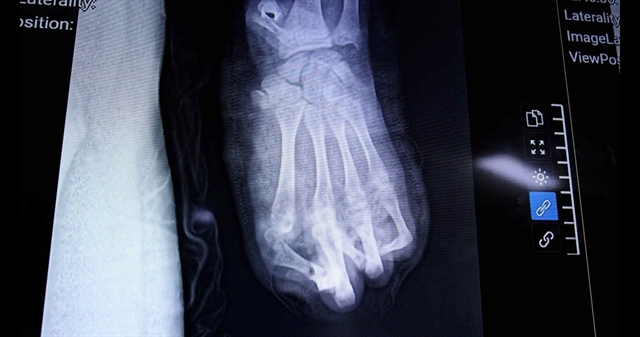

환자는 가나(Ghana) 보병 병사로 심한 우하복부 통증으로 입원해 파열 위험이 있는 급성 충수염으로 진단되어 즉시 수술이 결정되었다.

병원은 유엔표준 응급 프로토콜을 가동하고 유엔 남수단 임무단(UNMISS) 의료지휘부와 협의해 당일 밤 수술을 승인했다.

수술은 거의 한 시간 만에 성공적으로 끝났고 환자는 중환자실(ICU)로 이송되어 의식이 또렷하고 상태가 양호하다.